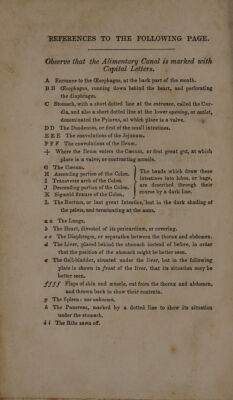

On indigestion and costiveness; a series of hints to both sexes, on the important, safe, and efficacious means of relieving diseases of the digestive organs by lavements ; with directions for the selection and use of apparatuses for their administration ; to which are added, observations on the mode of preserving health and prolonging life, by air, exercise, sleep, clothing, dieting, etc. Some general remarks, and useful hints, on the cause, prevention, and cure of obesity : also one hundred useful family prescriptions / [Edward Jukes].